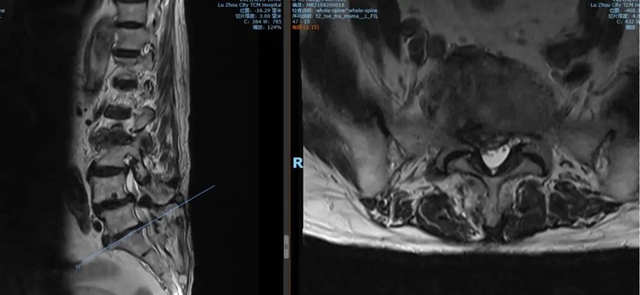

腰5骶1椎间盘MRI